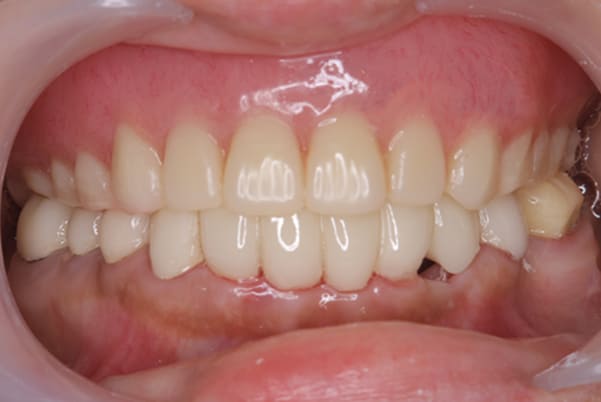

治療用入れ歯は患者様とご相談し、早急にお痛みをとり、お食事ができることをご希望されていたため、歯を抜くと同時に仮の入れ歯が入りお食事をされた後のお写真です。直ちに、お痛みを取り除き、お食事ができるような治療計画としました。

精密義歯は、歯をぬいたあと歯肉が治ってから、精密な入れ歯を作製しました。治療中も、仮の入れ歯があるため、普段の生活に支障がなく、また仮の入れ歯を実際使ってのご意見、ご希望(バネが気になる)をお聞きした上で、精密な義歯に、ご希望を反映し作製しました。

従来の方法では、歯を抜いてから入れ歯を作るまでは、歯茎の治りを待つため数か月かかりますが、患者様のご希望で、見た目、食べることに支障が出ないよう、抜歯と同時に入れ歯を装着し、歯がない期間がない入れ歯を作製したため、その日から、お食事や外出が可能となりました。

また、当然ではありますが、患者様も残りの歯をこれ以上失いたくないとのご希望が強く可能な限り、残りの歯に負担がかからない機能性を重視し、また、バネがなるべく見えない設計とし、機能と審美の両方に重きをおいた入れ歯を作製し、お痛みなく、お食事も召し上がられるようになりました。